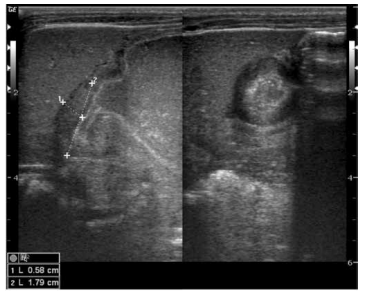

Criança de 8 anos, sexo masculino, vem apresentando história de infecção do trato urinário de repetição com relato de internação há 2 meses por febre

alta e dor lombar. Foi encaminhada ao setor de

radiologia pediátrica para investigação.

Após a análise do exame, pode-se afirmar que: